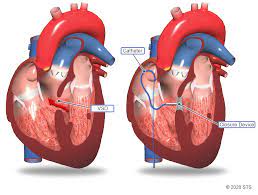

Value added benefits of the B.T. Shunt:

Overview

Package includes:

Days in hospital : 10 to 11 Days (For patient and one attendant)

Days in hotel : 14 Days (For patient and one attendant)

Room type in hospital : Shared

Room type in hotel : Private

Hotel category: Standard

Value added benefits of the BT Shunt:

Ø Doctor consultation charges

Ø Lab tests and diagnostic charges

Ø Room charges inside hospital during the procedure

Ø Surgeon Fee

Ø Nursing charges

Ø Hospital surgery suite charges

Ø Anesthesia charges

Ø Routine medicines and routine consumables (bandages, dressings etc.)

Ø Food and Beverages inside hospital stay for patient and one attendant.

Extra benefits:

ü Interpreter

ü Visa assistance

Ø Site tourism of the city

Ø Follow up with the doctor

Ø Airport pick up and drop

Ø Free online consultation with the doctor

Ø Priority appointments with the doctor

Ø Room upgrade from sharing to private